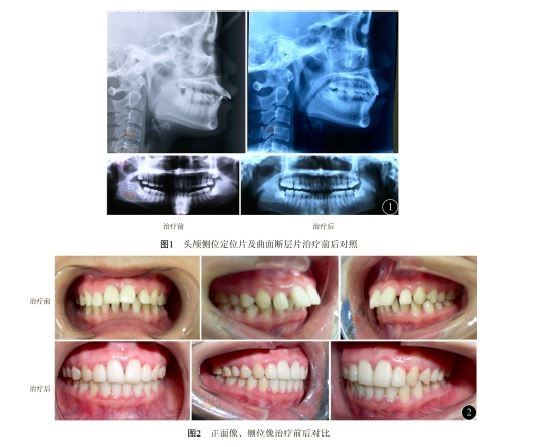

头颅定位片显示:牙前突移位成Ⅰ类骨面形,∠SNA=89.2°,∠SNB=85.5°,∠ANB=3.6°,上齿槽座欠丰满,垂直骨面形∠FMA=22.2°。全颌曲面断层片显示:全口牙牙槽嵴广泛水平吸收,牙槽嵴顶密度减低。前牙牙槽嵴吸吸收约为根长的1/3。

开唇露齿得到改善,前牙覆、覆盖关系正常,颏唇沟变浅,牙弓排列整齐,关系得到改善,骨面形改变不大。患者口腔卫生状况较好,软垢少量,牙周组织健康,牙龈无明显红肿,探诊无出血,牙齿无松动,牙周炎症得到明显控制。

∠SNA=85.6°,∠SNB=83.2°,∠ANB=2.4°,上齿槽座轻度改善,垂直骨面形∠FMA=18.5°。见图1,2。